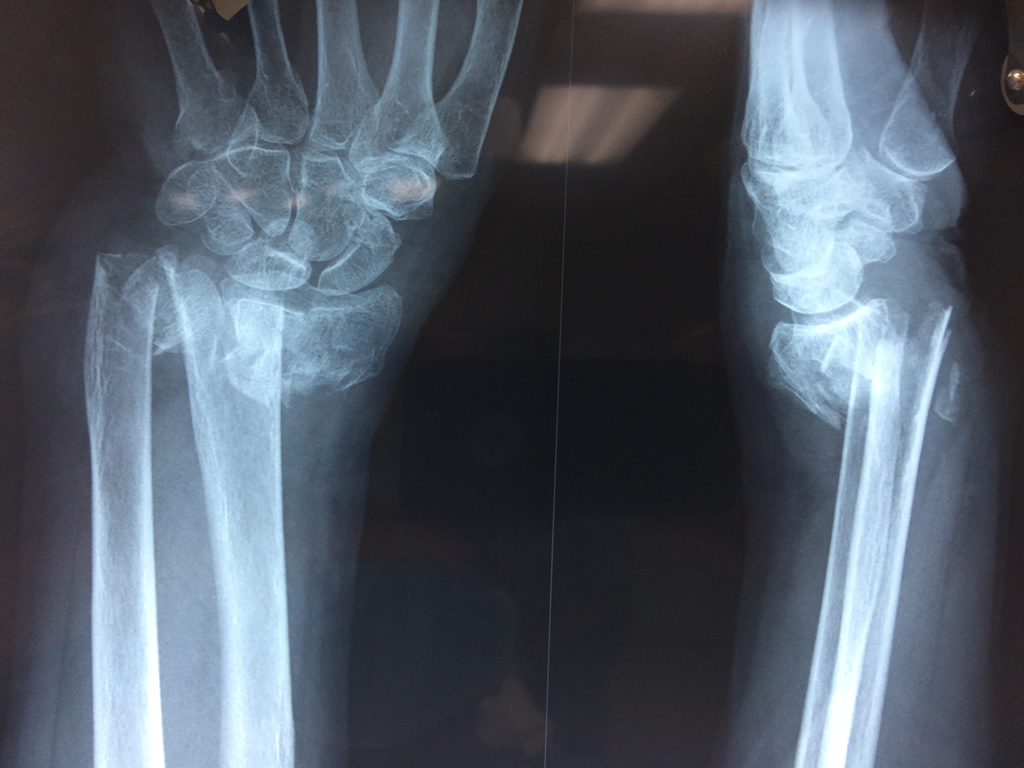

Cirugías de Calcaneo - Cirugías de Muñecas y Manos

Los procedimientos más comunes en cirugía de la mano son aquellos destinados a reparar traumatismos, incluyendo lesiones de tendones, nervios, vasos sanguíneos, y articulaciones; huesos fracturados; y quemaduras, cortes, y otros daños de la piel.